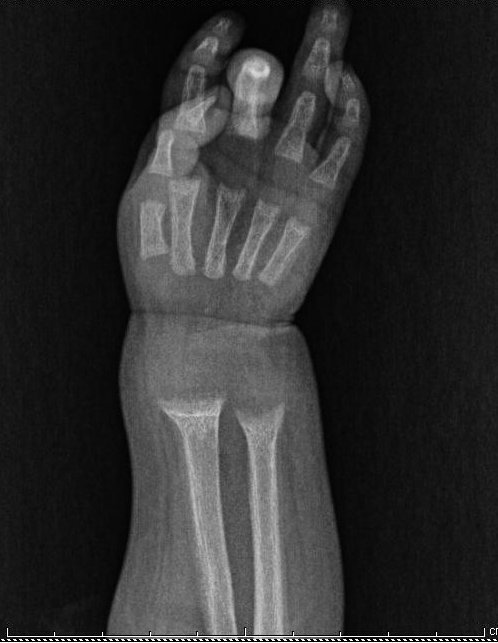

Caso clinico. M., un bambino di 10 mesi, veniva condotto in Pronto Soccorso per la presenza di febbre e tosse. All'ingresso il bambino si presentava in condizioni generali lievemente scadute; all'ascoltazione del torace si apprezzavano rantoli subcrepitanti a livello delle basi polmonari bilateralmente, ponendo diagnosi di bronchite catarrale. All'esame obiettivo si apprezzavano, inoltre, ipotonia generalizzata, ernia ombelicale, presenza di bozze frontali, braccialetto rachitico e rosario rachitico. Gli esami ematici eseguiti mostravano la presenza di deficienza di vitamina D severa (valori di 25-idrossivitamina D pressoch� indosabili, < 1,5 ng/ml, con vn 20-100), iperparatiroidismo (PTH 202 pg/ml, con vn 13-54), valori di 1,25-diidrossivitamina D ridotti (18 pg/ml con vn 20-65), ipocalcemia grave (calcio 7,4 mg/dl, con vn 8,6-10,2), ipofosforemia (fosforo 2,6 mg/dl con vn 2,7-4,5) ed infine livelli di fosfatasi alcalina aumentati (1019 U/l, con vn 40-130). I reperti clinici e biochimici permettevano quindi di porre diagnosi di rachitismo da deficienza di vitamina D con ipocalcemia (stadio III di Fraser). Un Rx del polso confermava la presenza di osteopenia, sfrangiamento e deformazione �a coppa� delle metafisi e assottigliamento degli spessori corticali. M. presentava diversi fattori di rischio di deficienza di vitamina D: il bambino era di origine senegalese, non aveva ricevuto profilassi con vitamina D ed era stato sottoposto ad allattamento al seno esclusivo prolungato (fino a 7 mesi). La madre di M. inoltre indossava il velo e non aveva ricevuto supplementazione con vitamina D durante la gravidanza.